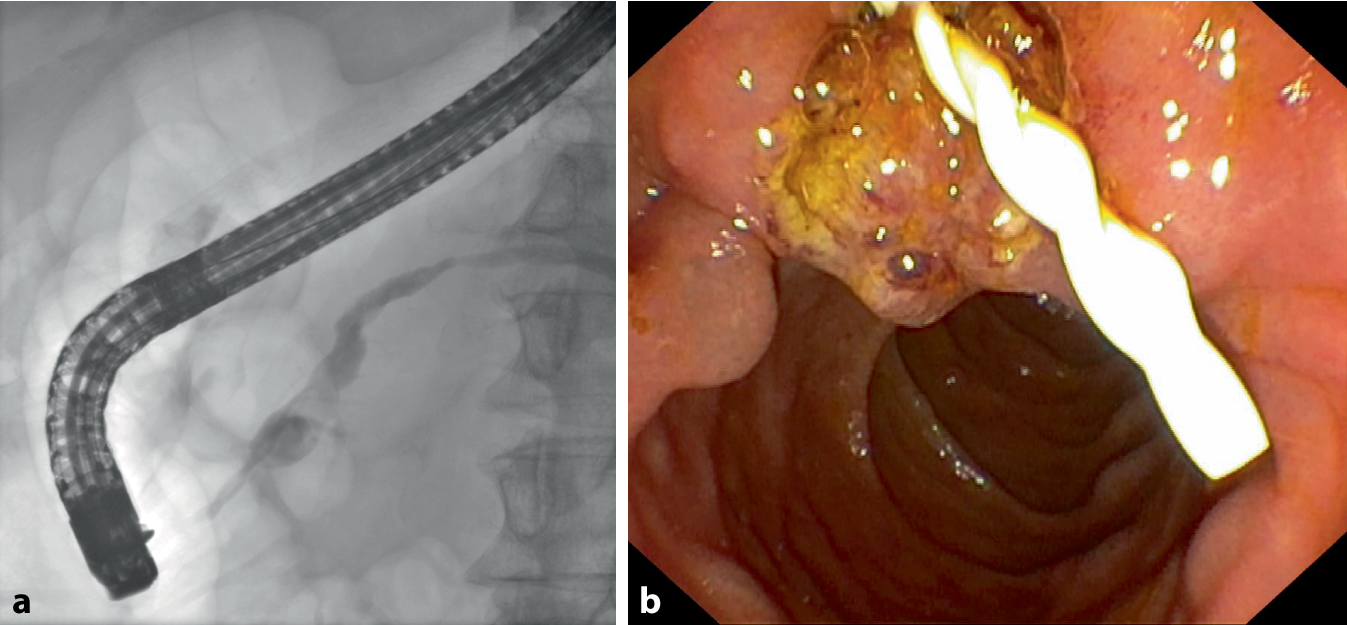

Die chronische/akute Schmerzsymptomatik sollte entsprechend dem WHO-Stufenschema therapiert werden. Auf der ersten Stufe sollten Paracetamol und Metamizol bevorzugt werden, auf Stufe 2 steht Tramadol zur Verfügung. Hier stehen zusätzlich auch Antidepressiva, wie Sertralin oder Antikonvulsiva, wie etwa Pregabalin oder Gabapentin, zur Verfügung [1, 4]. Stenosen mit Gangerweiterung und Pankreassteine können aufgrund der Obstruktion zu einer massiven Schmerzsymptomatik führen (Abb. 2). In diesem Fall ist neben der akuten Schmerztherapie eine Besprechung in einem multidisziplinären Board mit aktueller Bildgebung zur Therapieplanung notwendig. Vor der Eskalation auf Opioide (WHO Stufe 3) sollte ebenso eine Vorstellung an einer Spezialabteilung erfolgen, um potenziell endoskopisch/chirurgisch behandelbare Ursachen abzuklären. Zur Auswahl stehen endoskopische Interventionen mit Stenting, die extrakorporale Stoßwellenlithotripsie (ESWL) bzw. endoskopische Laserlithotripsie oder, je nach Komorbiditäten und Verlauf, die operative Sanierung [3]. Die ESWL wird für Pankreasgangsteine über 5 mm im Kopf‑/Körperbereich zur Anwendung gebracht. Das Stenting des Pankreashauptgangs kann bei schmerzhaften Stenosen mittels Plastikstents erfolgen [15]. Je nach Expertise stellt die Plexus-coeliacus-Blockade im fortgeschrittenen Krankheitsverlauf ebenso eine Option dar [4, 7].

Abb. 2

Pankreasgangstein mit nachgeschalteter Gangdilatation